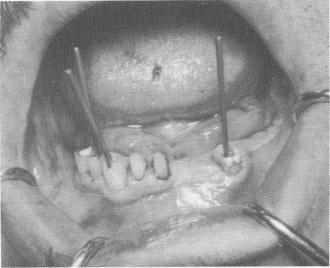

Fig. 13-30. An endodontic root stabilizer was set deeply into the bone existing below the loose incisor, immediately stabilizing it. All implants were set into the bone, and gold copings were placed over them.

Fig. 13-34. Three loose teeth were supported with endodontic stabilizers.